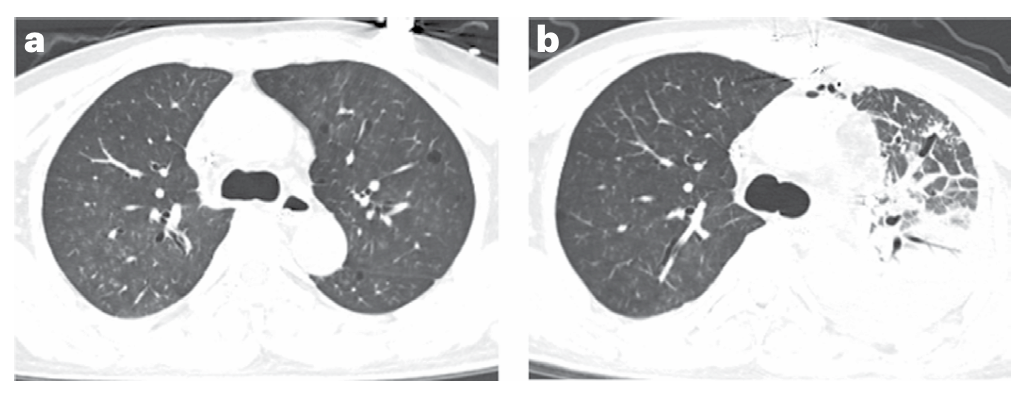

研究结果显示,移植猪肺在观察期内保持了基本功能,未出现超急性排斥反应或严重感染,标志着异种肺移植向临床转化迈出了关键一步。然而,术后24小时的胸部CT显示移植肺背侧区域实变(严重肺水肿),符合原发性移植物功能障碍(PGD)的表现,可能与缺血再灌注损伤有关。

图2. 移植后肺移植物透明度变化评估